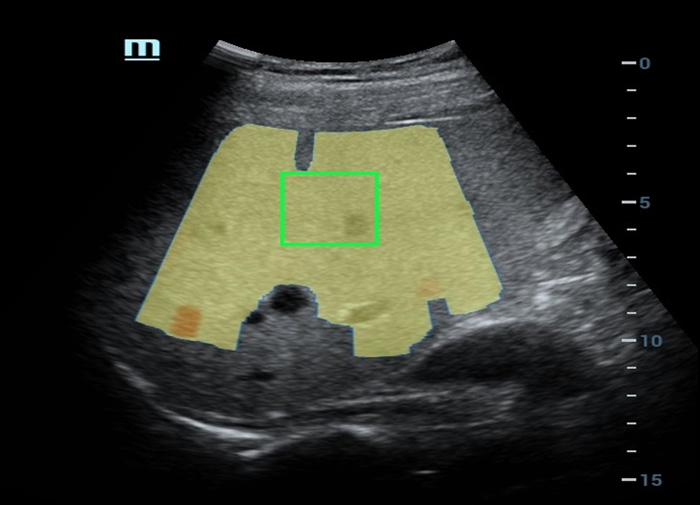

Multi-parametrisch lab voor leververvetting

Het multi-parametrische lab voor leververvetting biedt meerdere tools voor kwantitatieve analyse die gebaseerd zijn op verschillende akoestische technologie?n. Het maakt een kwantitatieve analyse van steatose mogelijk en verbetert de gevoeligheid van de detectie van leververvetting in een vroeg stadium.

Multi-parametrisch lab voor leververvetting

Een sprong vooruit in het onderzoek naar steatose